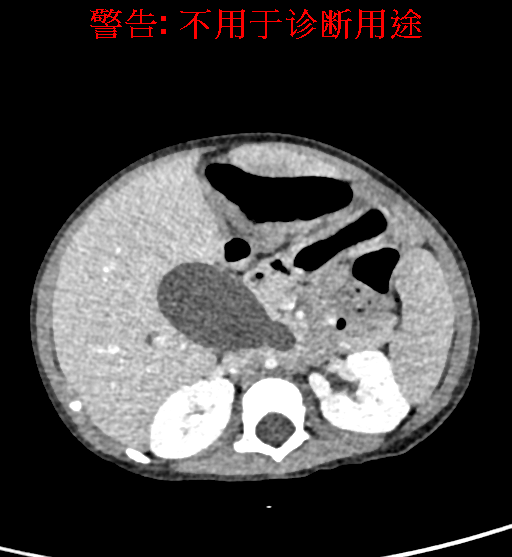

实验室检查: 血常规:WBC 16.16*109/L,NEU2.88*109/L,RBC3.76 1012/L,HB 92g/L, PLT 414*109/L 生化全套:ALT 50.00 U/L, AST 147.00 U/L, ALT/AST 0.34,LDH 367.00 U/L, ALB 36.91g/L, GGT 1297.00 U/L, ALP 1155.00 U/L, BIL-T 138.23 umol/L, BIT-D 97.01 umol/L, TBA 48.40umol/L,ADA 40.00U/L, PAB 121.40mg/L, BUN 1.98 mmol/L, CREA 17.00 umol/L 肝炎全套: 炎症反应标志物:CRP 7.27mg/l 诊疗过程: CT结果输入海信CAS系统后行3D重建及手术规划后,于2018-5-31全麻下行“胆总管囊肿切除+肝总管空肠吻合术”手术治疗: 术前三维重建及手术方案设计: 将0.625mm双源薄层CT资料的静脉期和动脉期Dicom格式文件导入海信CAS系统。 通过调节窗宽窗位调整CT序号,对肝实质,胆囊,下腔静脉,肿瘤,肝动脉、门静脉及肝静脉等进行三维重建;系统自动计算肝脏体积,肝脏体积为648.3ml,通过术前模拟手术,精准判断手术切除范围,进行精密术前规划及讨论后实施手术。 手术步骤: 麻醉成功后,患儿取平卧位,2.5%碘伏消毒手术区皮肤,铺无菌巾单。取右上腹纵口长约5m,切开皮肤、皮下织组,腹直肌前鞘、腹直肌,后鞘和腹膜。探查见:胆总管3×2cm大小,胆囊管迂曲,长约10cm。 剥离、切除胆囊,游离胆总管,将之横断:①近端即肝总管,剪裁后被吻合用;②远端游离切除囊肿内壁,直至胆总管开口于十二指肠处,冲洗后予以结扎缝扎。距treits韧带20cm处横断空肠:①近端与其远端25cm处的空肠侧壁行端侧双层吻合,吻合口通畅;②远端断端封闭,其侧壁剪开,并经横结肠后提至肝门处,与剪裁的肝总管行端侧双层吻合。缝合修补胆囊床及系膜裂孔,肝门部放置橡胶引流管一根。温盐水冲洗腹腔。检查无活动性出血,清点纱布器械无误,依次缝合腹壁各层。手术顺利,麻醉满意,出血不多,未输血,术后病人先进入麻醉恢复室,苏醒后回病房。手术时术者可开启Hisense CAS系统手势控制功能,对肝脏及胆囊解剖结构进行实时、全方观察、评估,起到术中导航作用。 术后病理: 1. (囊肿壁)囊肿性病变,囊壁部分区域衬覆柱状上皮。 2. 慢性胆囊炎。 3. 送检(肝门)淋巴结查见淋巴结1枚,呈反应性增生。 随访情况: 患儿术后2周恢复良好 术前CT检查:动脉期

静脉期